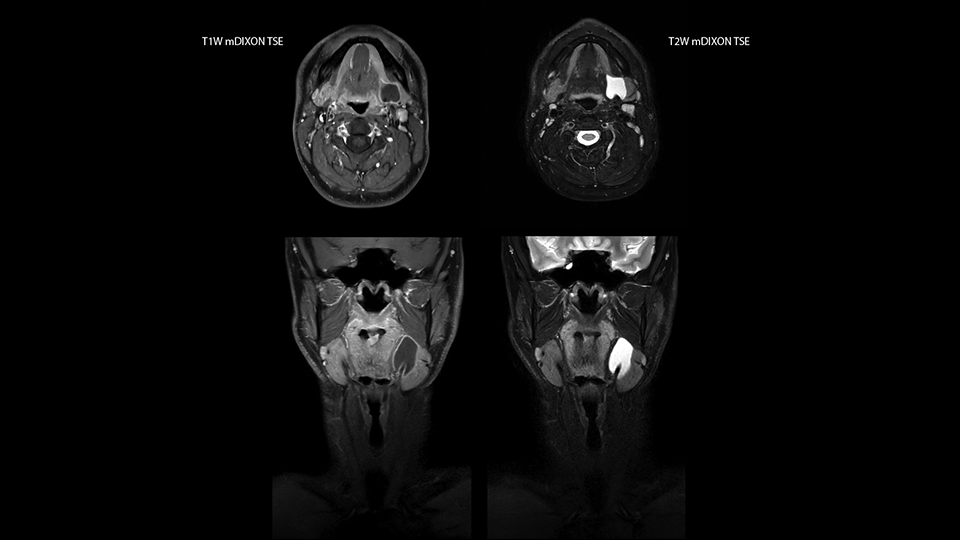

mDIXON TSE fat suppression helps DMG reduce repeats and supports diagnostic confidence

“Our DMG Lisle location includes a cancer center, so soft tissue neck scans, brachial plexus scans, and prostate scans are common. For these exams, mDIXON TSE provides excellent images with and without fat suppression all while helping us reduce repeats and work more efficiently,” Mr. Duffy says.

“With the 2-echo Philips mDIXON TSE the timing is short and the fatsat is very robust. The biggest thing is that you know your fat suppression will be good, even in thin patients or large patients that are off-center,” Mr. Sybesma says.

“Since we work in fixed time slots, not having to repeat scans is key for us,” Mr. Duffy adds. “With mDIXON TSE we get high quality results the first time – unless of course the patient absolutely jumps off the table. For us, that’s significant, because just a single repeat scan could put us behind schedule.

“mDIXON TSE raises our diagnostic confidence with its homogeneous

fat suppression. Neck exams and rheumatology patients are two examples where mDIXON TSE is especially useful,” Dr. Kaakaji says. “For us it’s also an efficiency boost in exams where we need pre and post T1-weighted images with great fat suppression.”